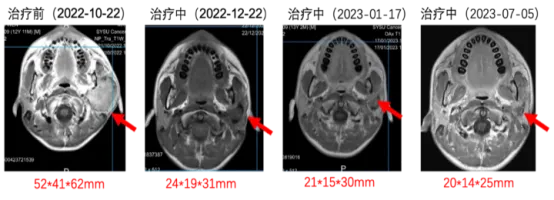

图2:8mg剂量组NTRK融合且既往未接受过TRK抑制剂治疗患者,左大腿梭形细胞肿瘤,TPM3-NTRK1融合,手术切除+化疗后进展,口服ICP-723(8mg)治疗一个周期后,首次肿瘤疗效评估为PR,靶病灶缩小37%,疗效在第二周期治疗后得以确认,目前患者正接受第11周期的治疗,疗效呈维持状态。